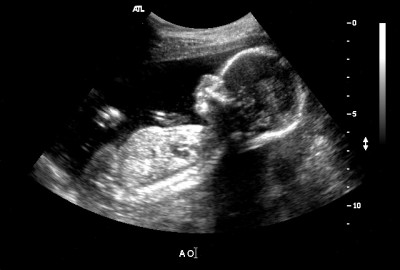

Ventre

À quoi ressemblent les estomacs à la dix-huitième semaine? C'est différent pour tout le monde. Certaines mères semblaient avaler une balle, tandis que d'autres semblaient s'étirer de haut en bas. C'est bon. Parfois, ils essaient de deviner par la forme de l'abdomen si une fille ou un garçon va naître.Et pourtant, seul un spécialiste en échographie peut vous dire avec certitude si cette semaine vous est prescrit une telle étude et que l'enfant veut partager un secret.

Photos d'échographie